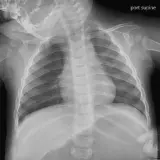

Chest Radiographs